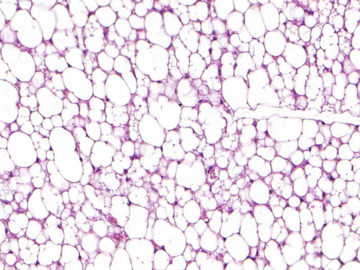

Die beigen Fettzellen mit dem Sisyphos-Mechanismus